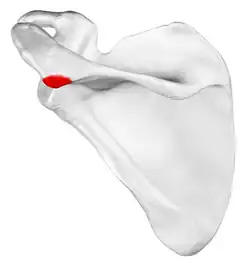

![]() Left scapula, posterior view. Acromion shown in red. | |

Acromion

In human anatomy, the acromion (from Greek: akros, "highest", ōmos, "shoulder", pl.: acromia) or summit of the shoulder is a bony process on the scapula (shoulder blade). Together with the coracoid process, it extends laterally over the shoulder joint. The acromion is a continuation of the scapular spine, and hooks over anteriorly. It articulates with the clavicle (collar bone) to form the acromioclavicular joint.[1]

The acromion forms the summit of the shoulder and is a large, somewhat triangular or oblong process, flattened from behind forward. It projects laterally at first, then curves forward and upward to overhang the glenoid fossa.[2] It starts from the base of acromion which marks its projecting point emerging from the spine of scapula.[3]